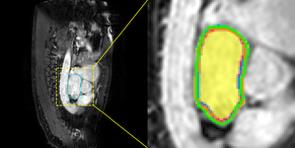

Accurate magnetic resonance imaging (MRI) segmentation is crucial for clinical decision-making, but remains labor-intensive when performed manually. Convolutional neural network (CNN)-based methods can be accurate and efficient, but often generalize poorly to MRI's variable contrast, intensity inhomogeneity, and protocols. Although the transformer-based Segment Anything Model (SAM) has demonstrated remarkable generalizability in natural images, existing adaptations often treat MRI as another imaging modality, overlooking these modality-specific challenges. We present SAMRI, an MRI-specialized SAM trained and validated on 1.1 million labeled MR slices spanning whole-body organs and pathologies. We demonstrate that SAM can be effectively adapted to MRI by simply fine-tuning its mask decoder using a two-stage strategy, reducing training time by 94% and trainable parameters by 96% versus full-model retraining. Across diverse MRI segmentation tasks, SAMRI achieves a mean Dice of 0.87, delivering state-of-the-art accuracy across anatomical regions and robust generalization on unseen structures, particularly small and clinically important structures.